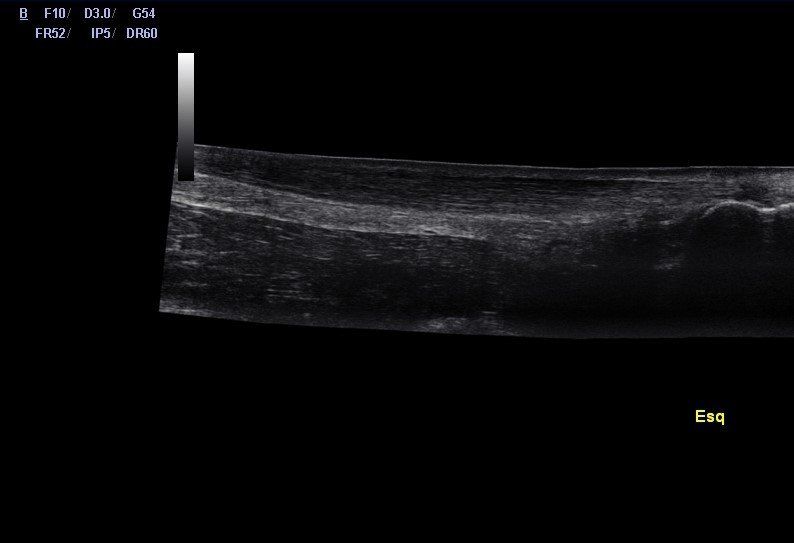

Por PUG-Msk 17 out, 2019

A tendinopatia do tendão de Aquiles (TA) representa entre 6 a 18% de todas as lesões que afetam os corredores, havendo uma maior prevalência em homens de meia idade.

A porção média do TA, localizada a cerca de 5/6cm da base do calcâneo, é a zona maioritariamente afetada. Na tendinopatia do TA, podemos encontrar uma degeneração do tendão, presença de rupturas tendinosas, bem como, a presença de neoneurovascularizações.

Quando existe uma neoneurovascularização no TA, na avaliação por imagem, podemos identificar a presença de Power Doppler positivo, ou seja, um sinal Doppler activo no lado ventral do TA. A neoneurovascularização pode ser definida como uma proliferação da rede nervosa e sanguínea (gordura de Kager’s), para o interior do tendão. Apesar de não existir uma associação absoluta entre dor e a neoneurovascularização intratendinosa, a evidência científica indica um nível de dor mais elevado em tendões hipervascularizados em comparação com tendões hipovascularizados.